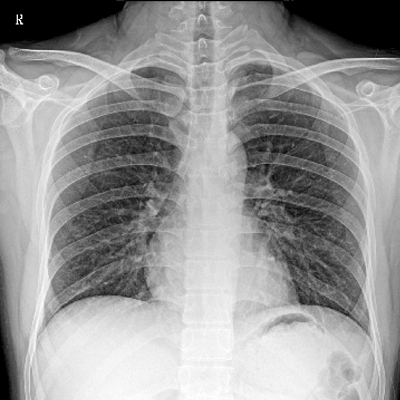

用于影像科、急診室、病房、ICU、手術(shù)室等多場(chǎng)景應(yīng)用。

● 數(shù)字化無線平板成像,操作簡(jiǎn)便,成像質(zhì)量高